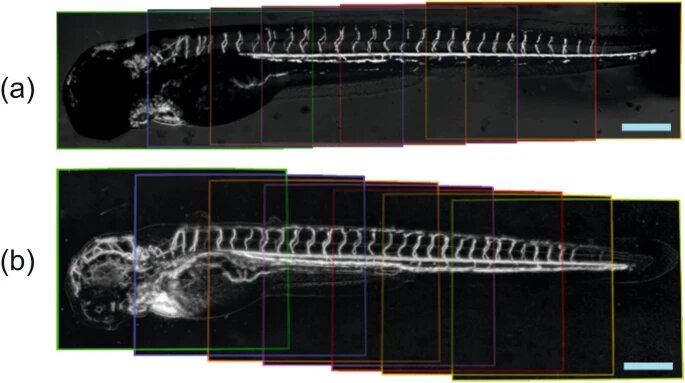

Фотографии сердечно-сосудистой системы данио-рерио, полученные с в диапазоне 400–1000 нм (а) и 900–1700 нм (b) / ©Volkov et al. / Scientific Reports, 2022

Чтобы охватить более широкий спектр, авторы установили в микроскоп два варианта приемников излучения — первый работал в диапазоне 400–1000 нанометров, а второй — 900–1700 нанометров. Затем исследователи сравнили эти два режима, наблюдая за сердечно-сосудистой системой большого количества взрослых рыбок данио-рерио. Эксперименты показали, что оба подхода позволяют проследить за динамикой биения сердца рыб, благодаря чему их можно использовать при изучении нарушений сердечного ритма.

Однако с помощью первого, более коротковолнового диапазона (400–1000 нанометров) не удается рассмотреть сосуды рыб сквозь пигментированные участки кожи, а также определить скорость кровотока в этих местах. С помощью регистрации и анализа более длинноволнового излучения, напротив, ученые получили детальные изображения даже самых мелких сосудов. Это объясняется тем, что окраска покровов оказывается «прозрачной» для длин волн в диапазоне 900–1700 нанометров.